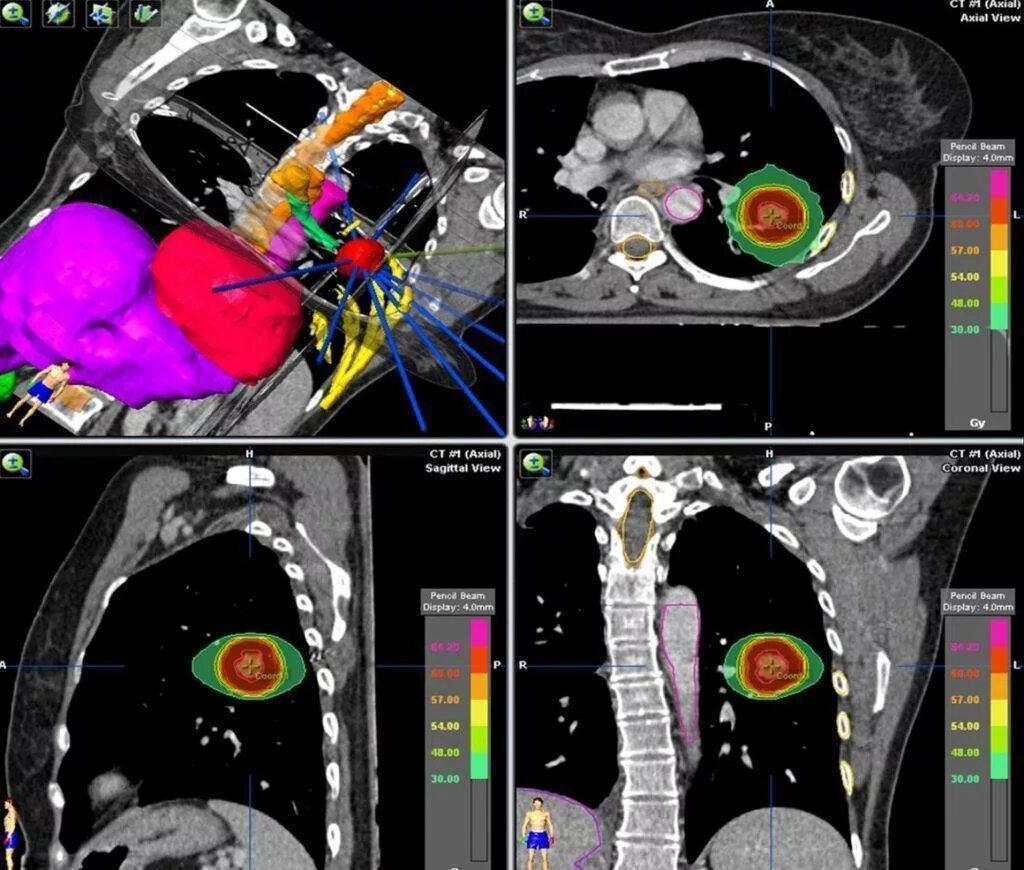

Лучевая при раке легких